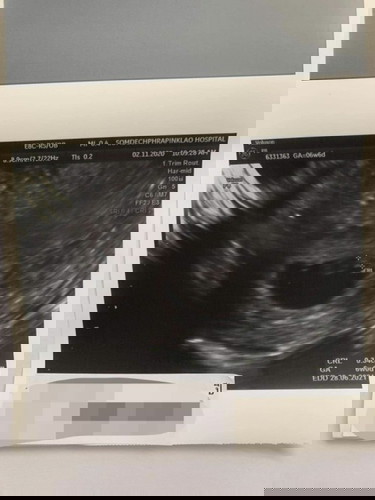

รูปนี้ซาวด์ครั้งแรก 6 สัปดาห์ครับ ทุกวันผมนี้เคลียดทุกวันเลยครับ แต่ละวันกว่าจะผ่านไปได้ ผมกลัวตลอดเลย ไม่รู้คิดมากไปหรือป่าว